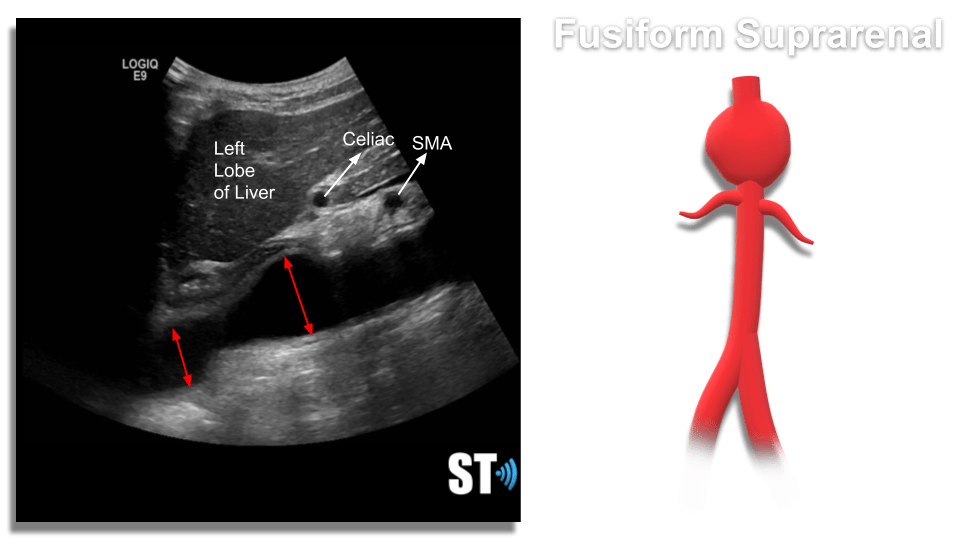

- Fusiform – Dilatation that spans a larger length of the vessel